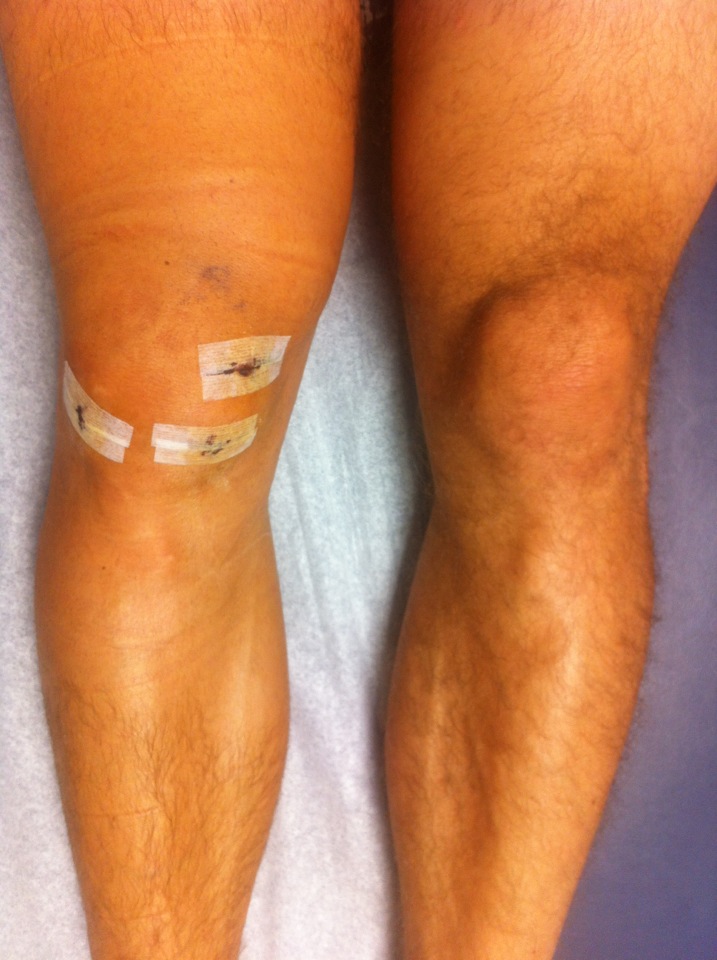

knee swelling, 2 days post op

The knee actually got drained after this photo, because I couldn’t move it due to the swelling/pain. I continued with the toradrol for the 5 days it was rx’d for (that’s the maximum legally allowed because it might shut down or damage my liver/kidneys/stomach etc) and continued with the norcal for 8 days post op(norcal=opiod and tylenol combo, they put a ton of tylenol in there so that it can’t be used recreationally or else you’d suffer serious liver damage).  I also kept icing it frequently, and did so for the 20-30 minutes suggested, this time it got really cold because there was no wrapping.  I was on crutches for 4.5 days. The doctors thought I was doing quite well compared to other people, as in my pain seemed less and swelling was less than normal.  I however thought I could do better.